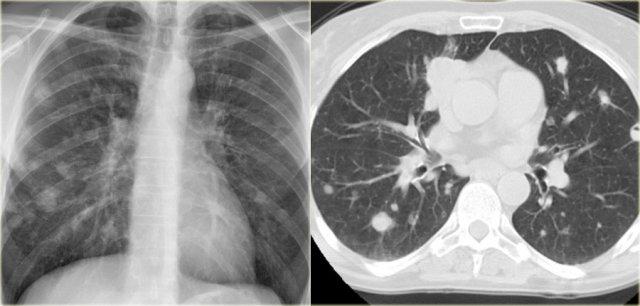

Các hình ảnh cho thấy ung thư biểu mô tế bào thận đã xâm lấn tĩnh mạch chủ dưới với sự lan rộng tiếp theo của bệnh đến phổi.

Đây là một bệnh nhân khác với di căn phổi lan rộng từ một khối ung thư có vị trí nguyên phát tại lưỡi.